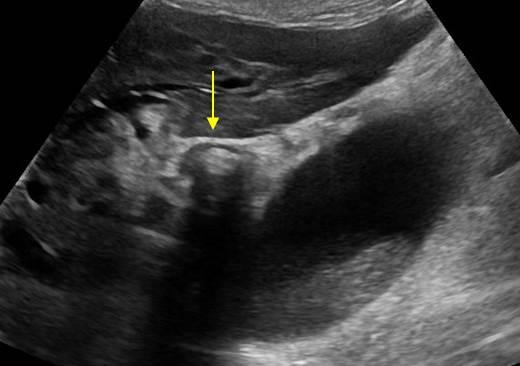

Viêm túi mật

Viêm túi mật - Ảnh 3

Viêm túi mật - Ảnh 4

» Thông tin: Nữ giới – 88 tuổi.

» Lâm sàng: Đau mạn sườn phải / Sốt.